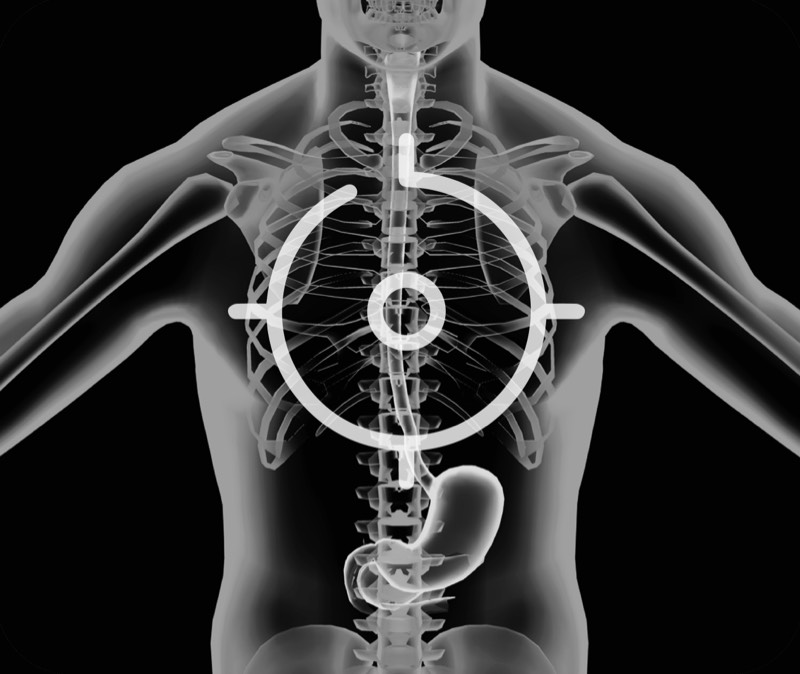

超声电子上消化道内窥镜

卓越的宽频设计,满足医生探查不同深度的组织和器官